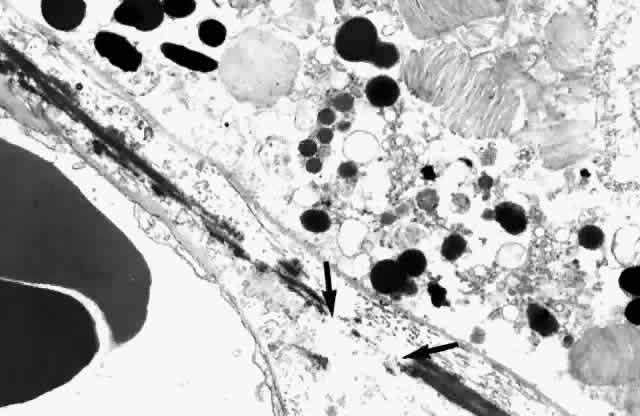

The elastic layer, the middle layer of Bruch's membrane, is a dense, irregularly interrupted band composed of interwoven elastic tissue fibers of various thickness. The elastic fibers are ultrastructurally composed of long and straight rods with a homogeneous core and dense cortex. Variably sized spaces are present between the elastic fibers. They provide passageways for collagen fibers from the inner collagenous zone to the outer collagenous zone and into the intercapillary septa and subcapillary zone of the choriocapillaris (Fig. 10). The elastic tissue and collagenous layers of Bruch's membrane become circularly oriented around the edge of the optic nerve.

Fig. 10. Passageway between elastic fibers (between arrows). (× 12,900)